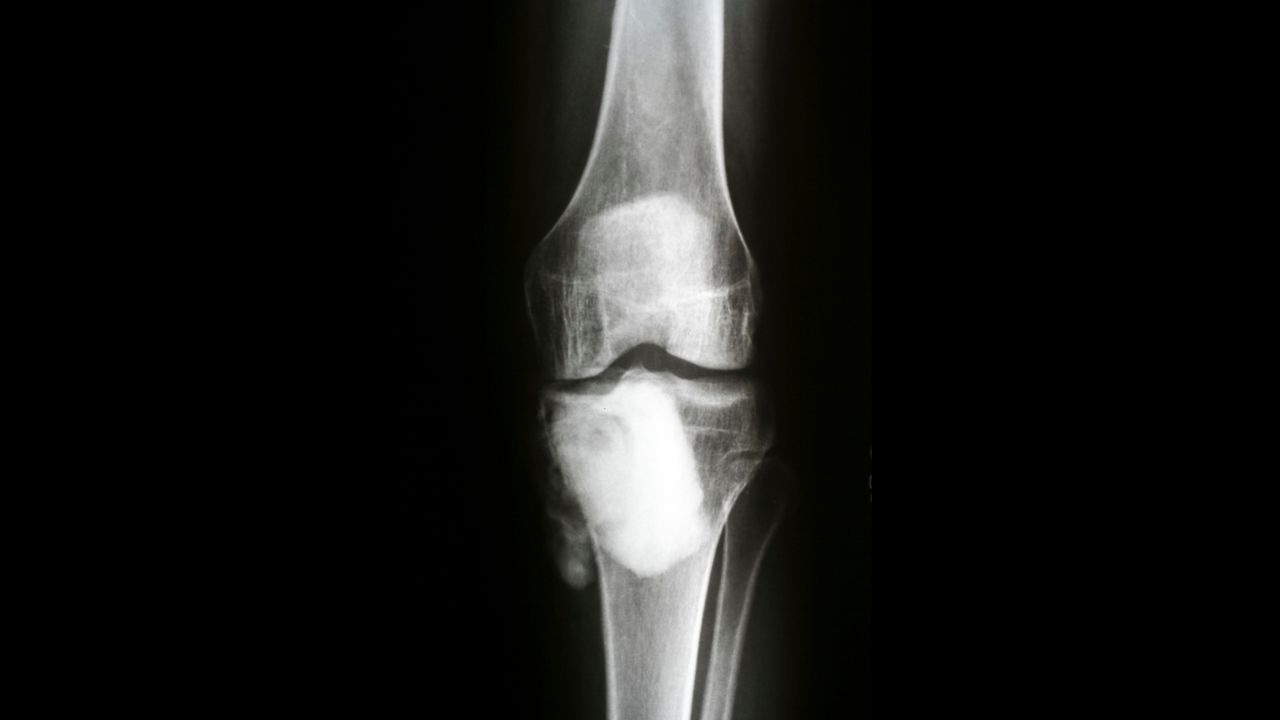

تومور ژانت سل استخوان یا جاینت سل تومور یک تومور غیرسرطانی، خوشخیم و نادر است که رشد بسیار سریعی دارد و در انتهای استخوانهای بلند مانند ران و زانو ایجاد میشود.

طبق مطالعات، تومور سلول ژانت استخوان از سلولهای چند هستهای بهنام ژانت سل تشکیل شده است و بیشتر، افراد در سنین ۲0 تا ۴۰ سال را درگیر میکند. جاینت سل تومور، استخوانها را ضعیف میسازد و درد، ناراحتی و تورم بهدنبال دارد؛ این موارد به شکستگی استخوان منجر میشوند.

- اشعه ایکس: با تابش امواج الکترومغناطیسی به بافتها، تصاویری دقیق از اندام و استخوانها تهیه میشود.